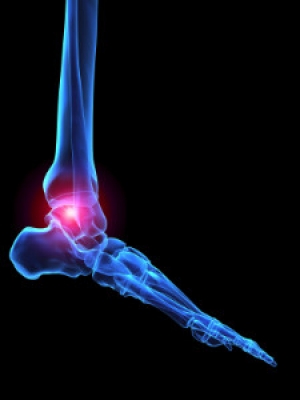

The tarsal tunnel is a canal that exists between the ligaments that spans across the foot and a portion of the bone. The nerves and tendons that are inside this tunnel allow mobility and enable the foot to easily point and flex. If a specific nerve called the tibial nerve inside this canal should become compressed, typically resulting from an injury, this condition is referred to as tarsal tunnel syndrome. Having flat feet is a possible reason for this condition, causing the tibial nerve to become strained. Certain health issues, such as arthritis and diabetes, may also cause the nerve to endure swelling and increased pressure. The nerve must be allowed to heal properly, and this may be accomplished by wearing a brace or supportive shoes. The discomfort that is experienced may be indicative of other foot-related conditions, so it’s advised to consult a podiatrist for a proper diagnosis

Tarsal tunnel syndrome, which can also be called tibial nerve dysfunction, is an uncommon condition of misfiring peripheral nerves in the foot. The tibial nerve is the peripheral nerve in the leg responsible for sensation and movement of the foot and calf muscles. In tarsal tunnel syndrome, the tibial nerve is damaged, causing problems with movement and feeling in the foot of the affected leg.

Tarsal tunnel syndrome is a condition in which there is a compression of the posterior tibial nerve. The posterior tibial nerve runs along the inside of the into the foot. Tarsal tunnel syndrome is named for the tarsal tunnel, which is a thin space along the inside of the beside the bones. This space contains various nerves, arteries, and tendons, and includes the posterior tibial nerve. The tibial nerve is the peripheral nerve in the leg responsible for sensation and movement of the foot and calf muscles. In tarsal tunnel syndrome the tibial nerve is compressed, causing tingling or burning, numbness, and pain.

Common causes of tarsal tunnel syndrome involve pressure or an injury. Injuries that produce inflammation and swelling in or around the tunnel may place pressure on the posterior tibial nerve. Direct pressure on the tibial nerve for an extended period of time, sometimes caused by other body structures close by or trauma to the tibial nerve, can result in tarsal tunnel syndrome. Diseases that damage nerves, such as diabetes or arthritis, may cause tarsal tunnel syndrome. Those with flat feet are at risk for developing the condition, as the extra pressure and strain placed on the foot may compress the posterior tibial nerve.